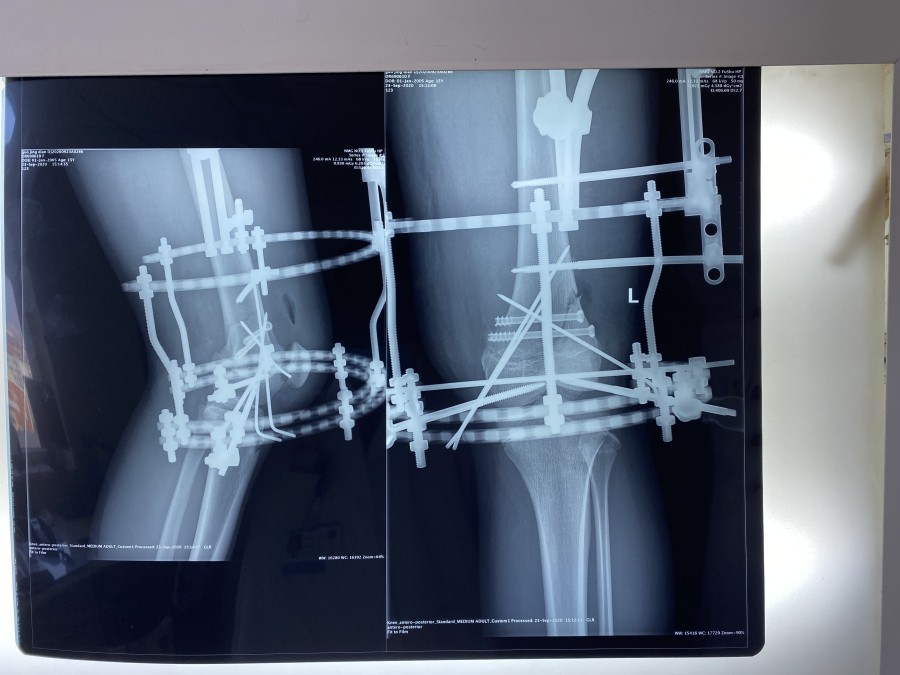

幸运的是MRI检查没有膝关节韧带和半月板的损伤。考虑到小郭的职业生涯,不能出现医源性肌肉等软组织损伤、以及运动员发达的大腿肌肉和术后快速康复的需求等等,小儿骨科团队进行了认真的术前讨论,9月21日,由韦宜山主任主刀实施了闭合复位经皮空心螺钉联合克氏针辅助Ilizarov环形外固定架手术治疗。手术非常成功,骨折端完全解剖复位,术后第1天小郭即开始床上膝关节主动和被动活动,第3天已可下地进行短时间不负重训炼,术后第10天已经可以独立扶双拐行走,10月9日,小郭顺利康复出院。术后,小郭一日三餐由91直播 营养部免费提供营养餐,病区护理人员专人负责陪护。